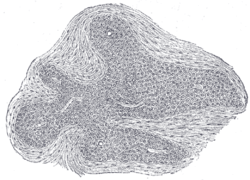

![]() Section of an irregular nodule of the glomus coccygeum. X 85. The section shows the fibrous covering of the nodule, the bloodvessels within it, and the epithelial cells of which it is constituted. | |

It is about 2.5 mm. in diameter and is irregularly oval in shape; several smaller nodules are found around or near the main mass.

It consists of irregular masses of round or polyhedral cells epitheloid cells, which are grouped around a dilated sinusoidal capillary vessel.